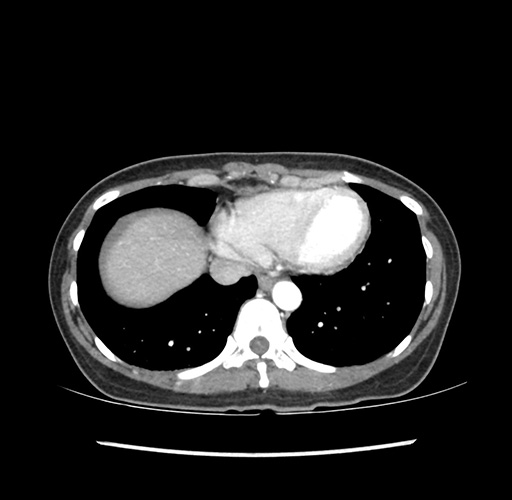

Imaging Analysis

Look through the patient's CT scan to identify any areas of concern for the necessary procedure.

Based on your CT findings, which issue(s) would give reason for "planned slowing down moment(s)" in this case?

Considering a standard left lateral sectionectomy procedure, what step(s) of the operation would you do differently in this case ?